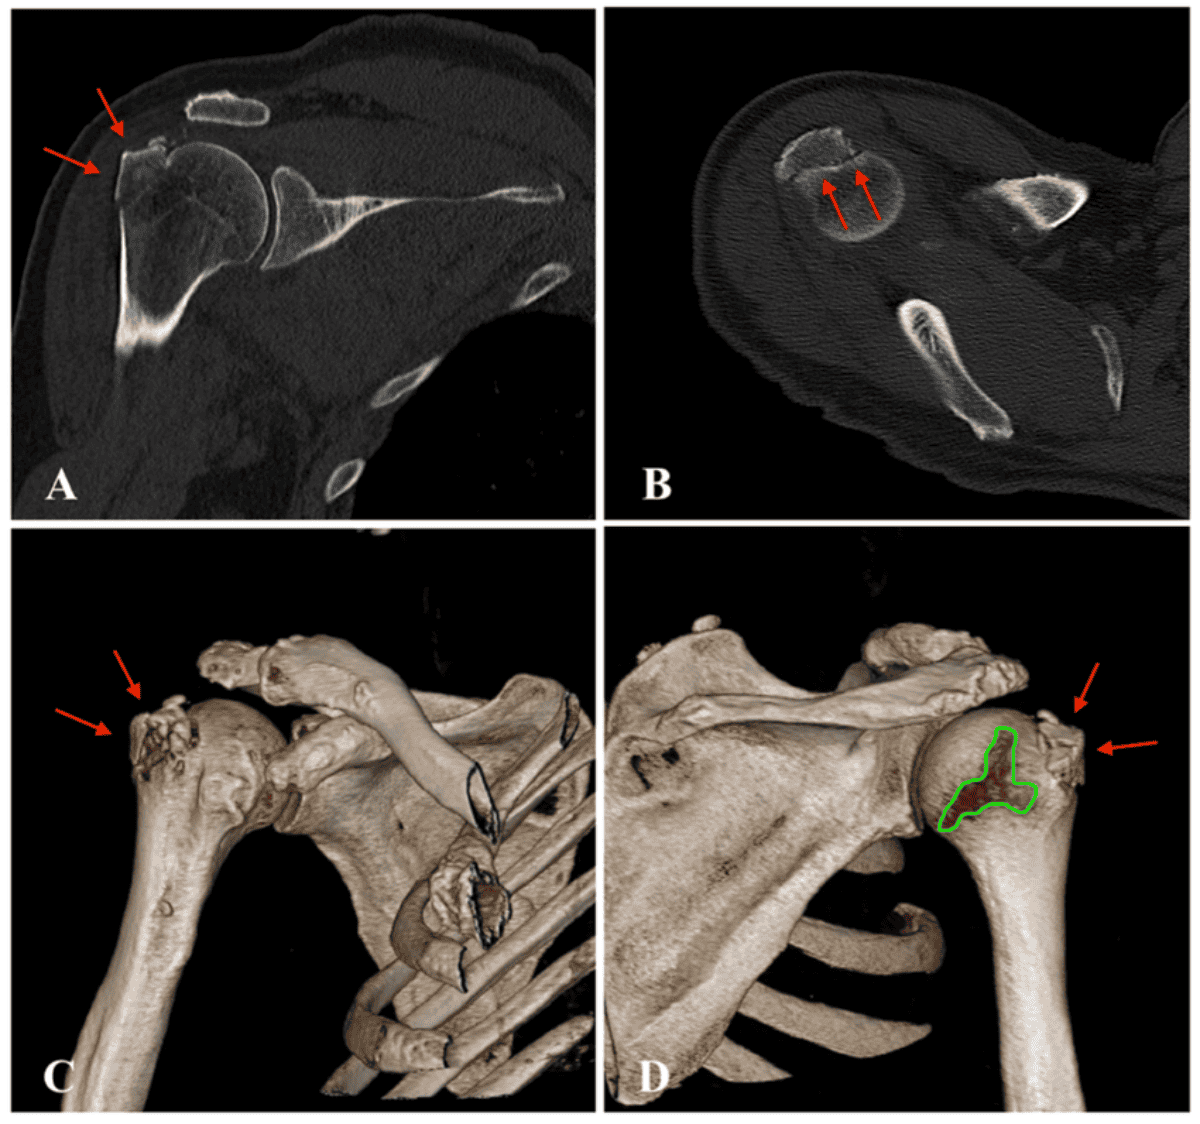

Sin embargo, hay casos que pueden requerir, de forma adicional, de una resonancia magnética (RM), una tomografía axial computarizada (TAC), o una ecografía para evaluar los tejidos blandos.

Provencher, M.T. et al recomiendan realizar una tomografía computarizada (TC) en 3D para evaluar la morfología y el potencial de la lesión causada por el hombro dislocado (18).

Otro estudio explica las distintas técnicas de diagnósticos efectivas para este tipo de luxación. Entre ellas destacan: proyecciones radiográficas útiles, técnicas de TC 3D, secuencias de RM y uso de artrografía por RM o TC. Además, se utilizan varios criterios para calcular los defectos óseos, como por ejemplo, el porcentaje de pérdida glenoidea, así como el tamaño de la luxación de hombro.

La TC es la referencia para realizar una valoración ósea; la RM/ARM es superior para lesión labroligamentaria y para realizar un examen adicional del manguito rotador.